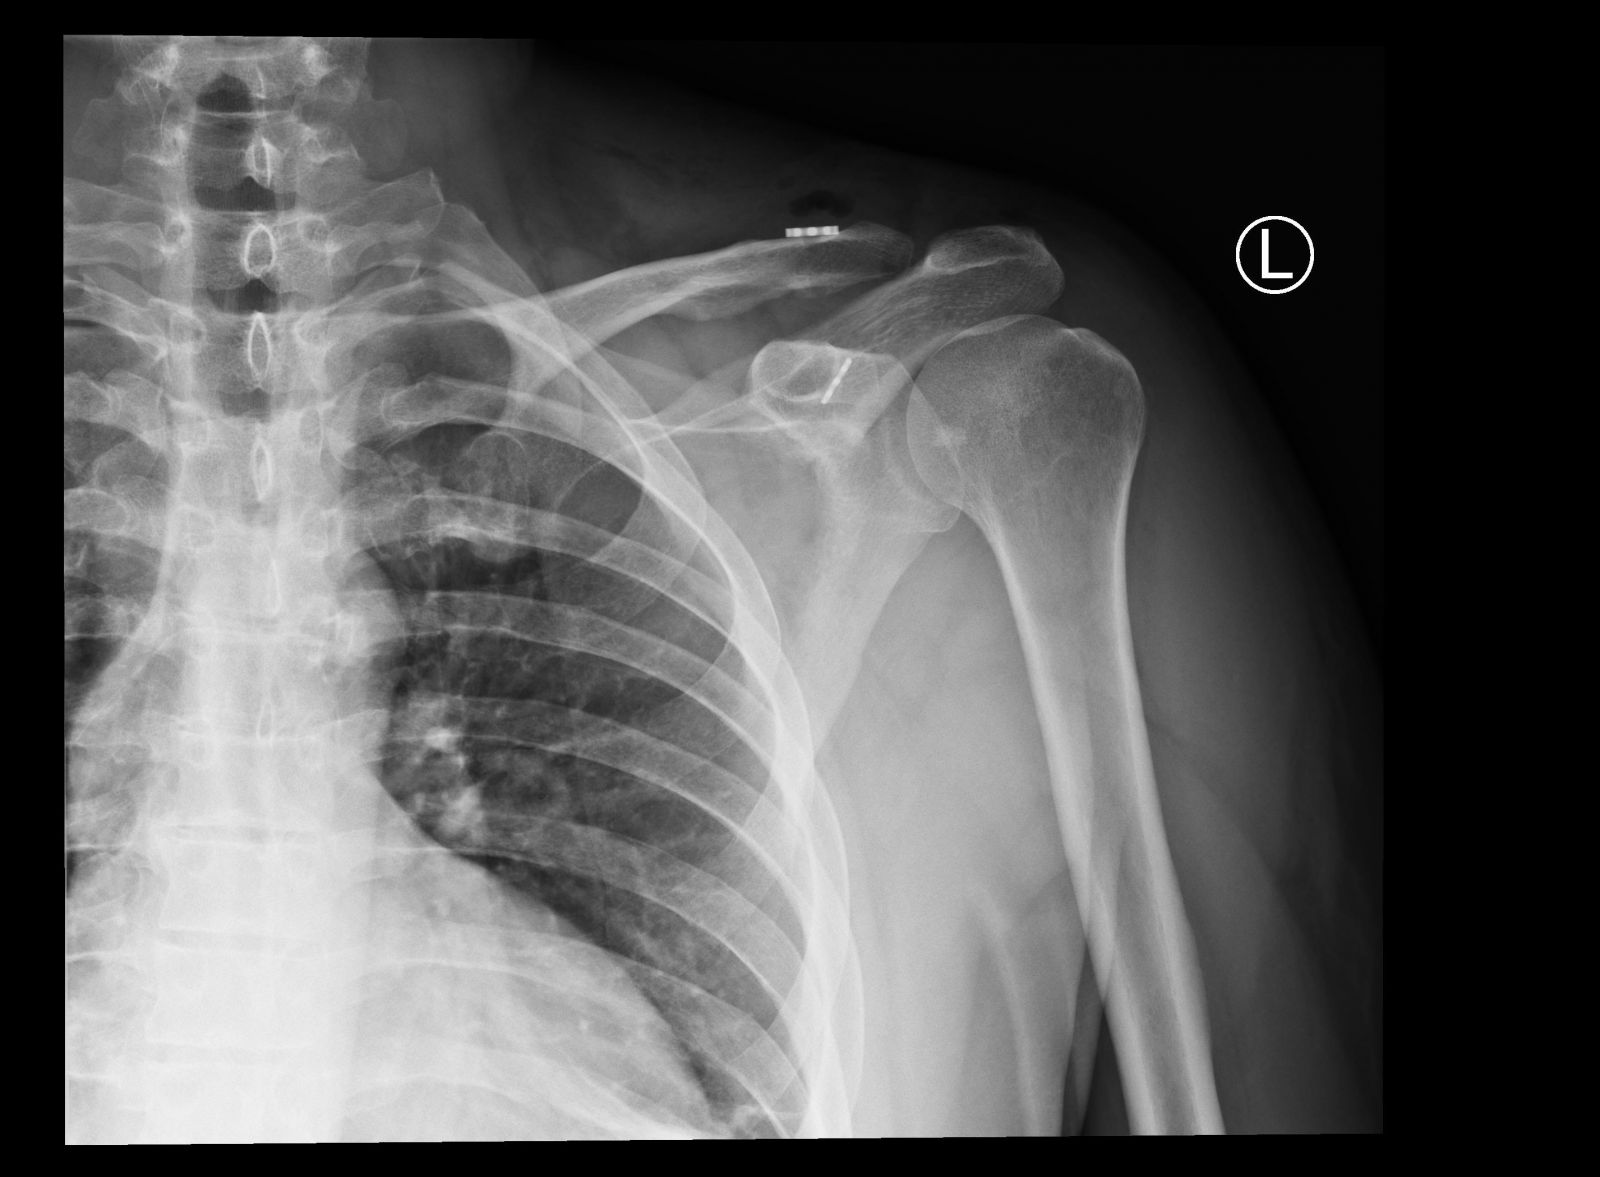

To był kolejny udany zabieg na bloku operacyjnym w Szpitalu Miejskim im. Jana Garduły w Świnoujściu. – Przeprowadziliśmy zabieg naprawczy zwichniętego stawu barkowo-obojczykowego u 41-letniego mężczyzny. Kontuzję odniósł po upadku podczas jazdy na nartach – informuje lek. Krzysztof Pobłocki, który od niedawna przyjmuje i operuje pacjentów w świnoujskiej placówce.

Operowany był pan Marcin. – Zabieg wykonaliśmy z niedużego cięcia nad obojczykiem, w asyście artroskopii stawu ramiennego. Zwichnięcie zostało nastawione i ustabilizowane specjalnym nićmi oraz dwoma mini guziczkami – wyjaśnia K. Pobłocki.

Zwichnięcie stawu barkowo-obojczykowego jest częstym uszkodzeniem okolicy barku. Najczęściej spowodowane jest bezpośrednim urazem; jak uderzenie czy upadek na bark. Dochodzi do uszkodzenia więzadeł łączących obojczyk z wyrostkiem kruczym i barkowym łopatki, w wyniku czego dalsza część obojczyka wystaje nad powierzchnię stawu.

– W badaniu widzimy zwykle charakterystyczny objaw schodka czy klawisza i wtedy z reguły decydujemy się na leczenie operacyjne. Do rozpoznania wystarczy nam zdjęcie RTG w projekcji od przodu – dodaje K. Pobłocki.

Na zdjęciach: staw barkowo-obojczykowy po urazie i po dokonanym w naszym szpitalu zabiegu.